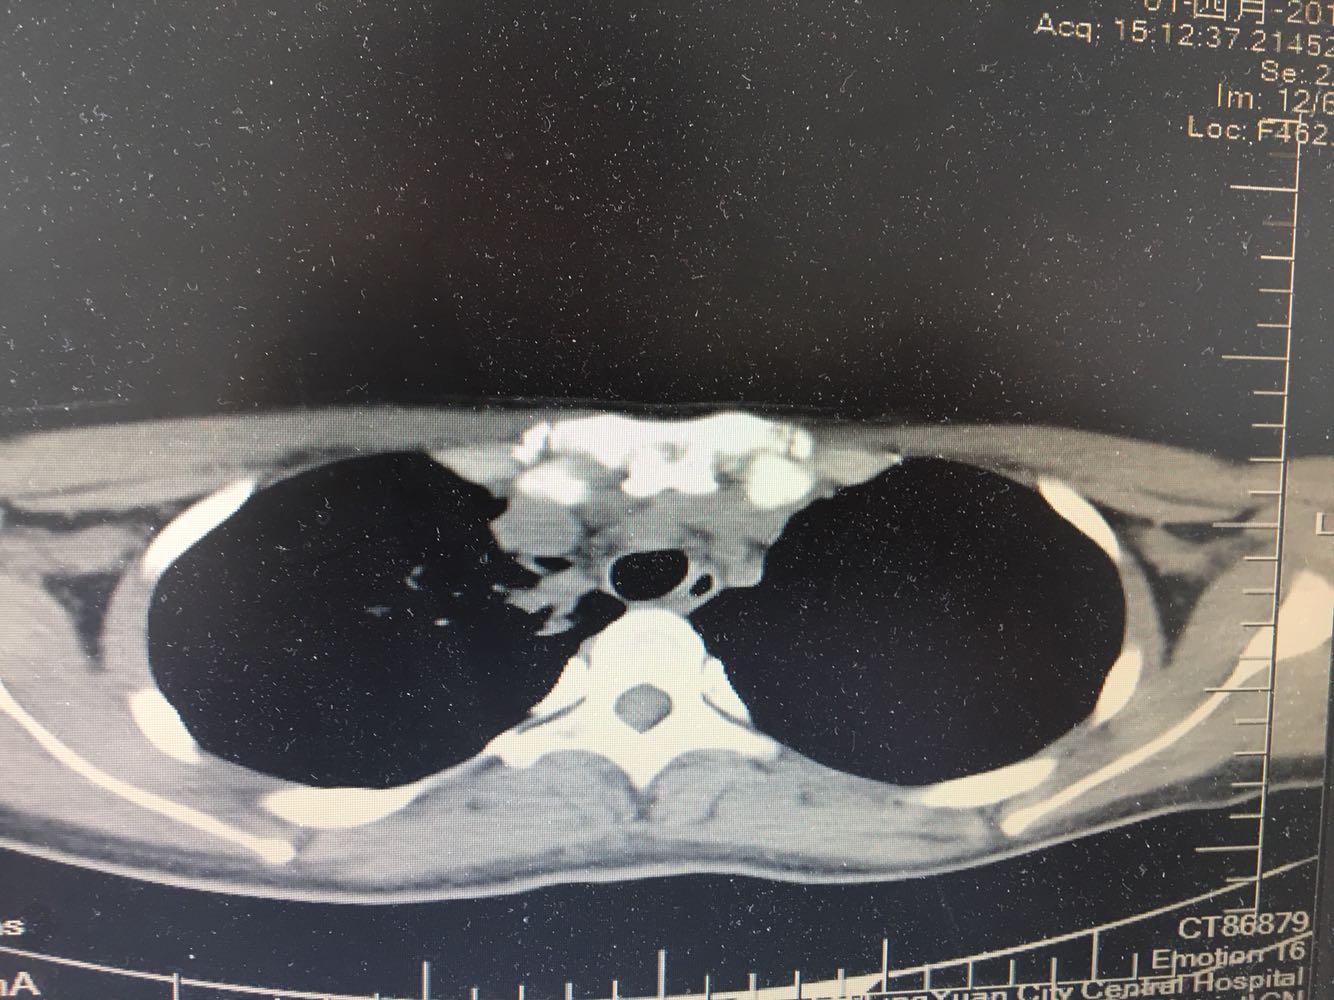

女,26岁,咳嗽1周,咳痰不畅,咽喉痒,口服阿莫西林无好转,昨日发热,体温38.5摄氏度,于门诊查肺CT后以肺炎收入院,病来无盗汗,无咳血,无消瘦及乏力,无头痛,无肢体酸痛,饮食睡眠可,二便正常

神清言明,咽部无充血,扁桃体不大,双肺呼吸音清,无罗音,服软无压痛。

支原体肺炎?肺结核?

支原体抗体1:160,结核抗体弱阳性。支原体肺炎个别可见上叶病变,该患无结核中毒症状,考虑支原体肺炎可能性大,但肺尖为结核好发部位,需要抗炎治疗后复查观察疗效。